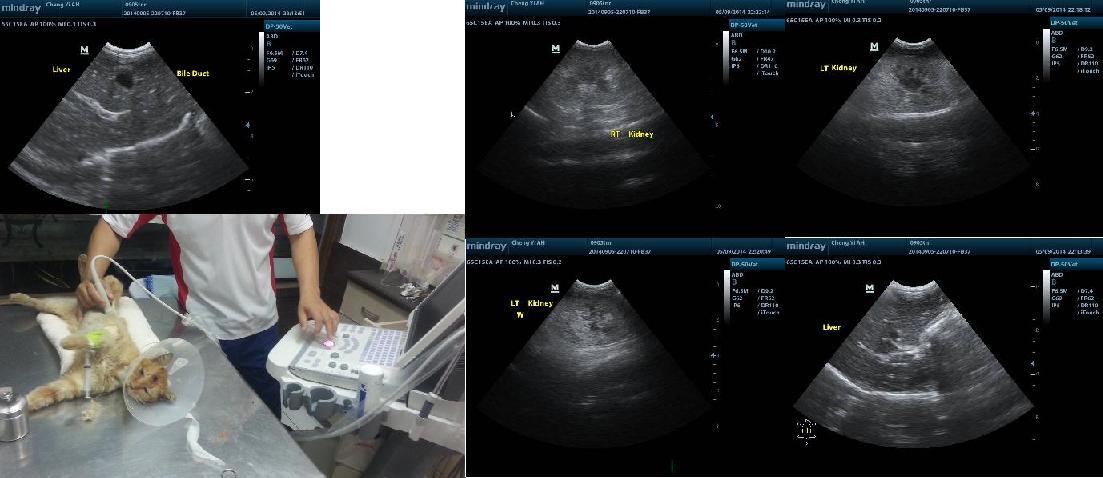

驗血數值有偏低但還在安全範圍....但食慾變差醫生趁麻醉時安裝食道管灌食..也照了X光..發現肝臟又變大..

9/18 X光 ----------------------- 300